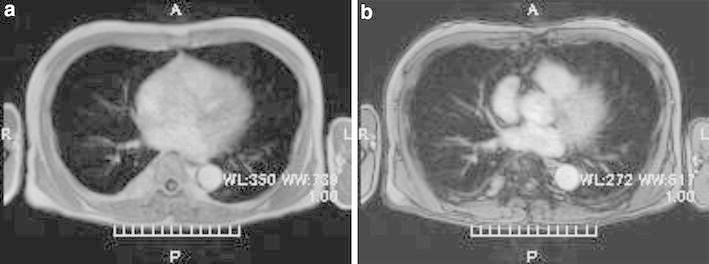

Fig. 3.

Magnetic resonance imaging (MRI). According to T1 enhanced dual image at (TR165, TE4.8), the tumor is revealed as high intensity (Fig. 3a), however, at (TR165, TE2.3) it is revealed as partially low intensity (Fig. 3b). It suggests that the tumor contains fat component